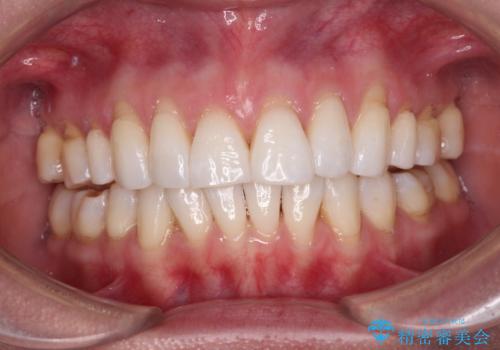

- 上の前歯の出っ歯を治したいとのことで来院された患者様です。

後戻りによる再矯正というもともあり、インビザラインを希望されていました。

上顎の歯は後方移動とIPR(歯と歯の間を削る)によって口元が引っ込むように、下顎は歯列全体の拡大とIPRによって上顎とバランスよく咬み合うように設計し、インビザラインにより治療を行うこととしました。

治療を開始して暫くして、勤務先から2年以上帰国することができず、それまでの移動がほとんど後戻りしてしまい、帰国後に再度後戻りをリカバリーするための治療を行うこととなりました。

5年以上の治療期間がかかりましたが、気になっている部分を改善することができました。